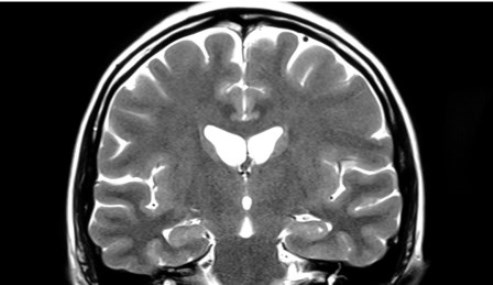

El equipo de investigación analizó datos del Estudio sobre el Envejecimiento de Mayo Clinic, una iniciativa de investigación a largo plazo que comenzó en 2004. Identificaron poco más de 1.000 mujeres que se habían sometido a imágenes con tensor de difusión, una técnica de resonancia magnética que evalúa la integridad de la materia blanca del cerebro. De ellas, 907 no se habían sometido a ooforectomía bilateral premenopáusica (PBO). Los participantes del estudio se agruparon de la siguiente manera:

Los investigadores encontraron una integridad reducida de la materia blanca en múltiples regiones del cerebro entre las mujeres que se sometieron al procedimiento quirúrgico antes de los 40 años. Se observaron tendencias similares en mujeres que se sometieron a PBO entre los 46 y 49 años. No hubo diferencias en las vías cerebrales para las mujeres que tuvieron PBO a edades 40 a 44 en comparación con las mujeres que no se sometieron al procedimiento.

Hasta el 80% por ciento de las participantes a quienes se extirparon los ovarios también tenían antecedentes de terapia de reemplazo de estrógenos (TRE). Sin embargo, a pesar del uso de TRE por parte de estas mujeres, la integridad de su sustancia blanca permaneció disminuida.

Según los investigadores, esto sugiere que la pérdida de testosterona, más que de estrógeno, desempeña un papel fundamental en la salud del cerebro, indica el estudio, publicado en la revista Alzheimer’s & Dementia.